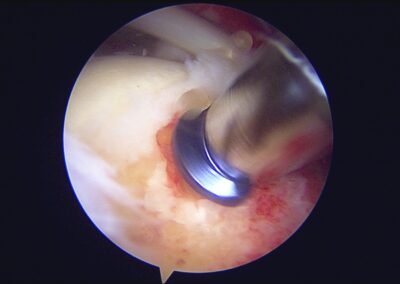

GalleryShoulder rotator cuff repair Meniscus root repair Meniscus repair Bankart repair for recurrent shoulder dislocation ACL reconstruction Machines Instruments